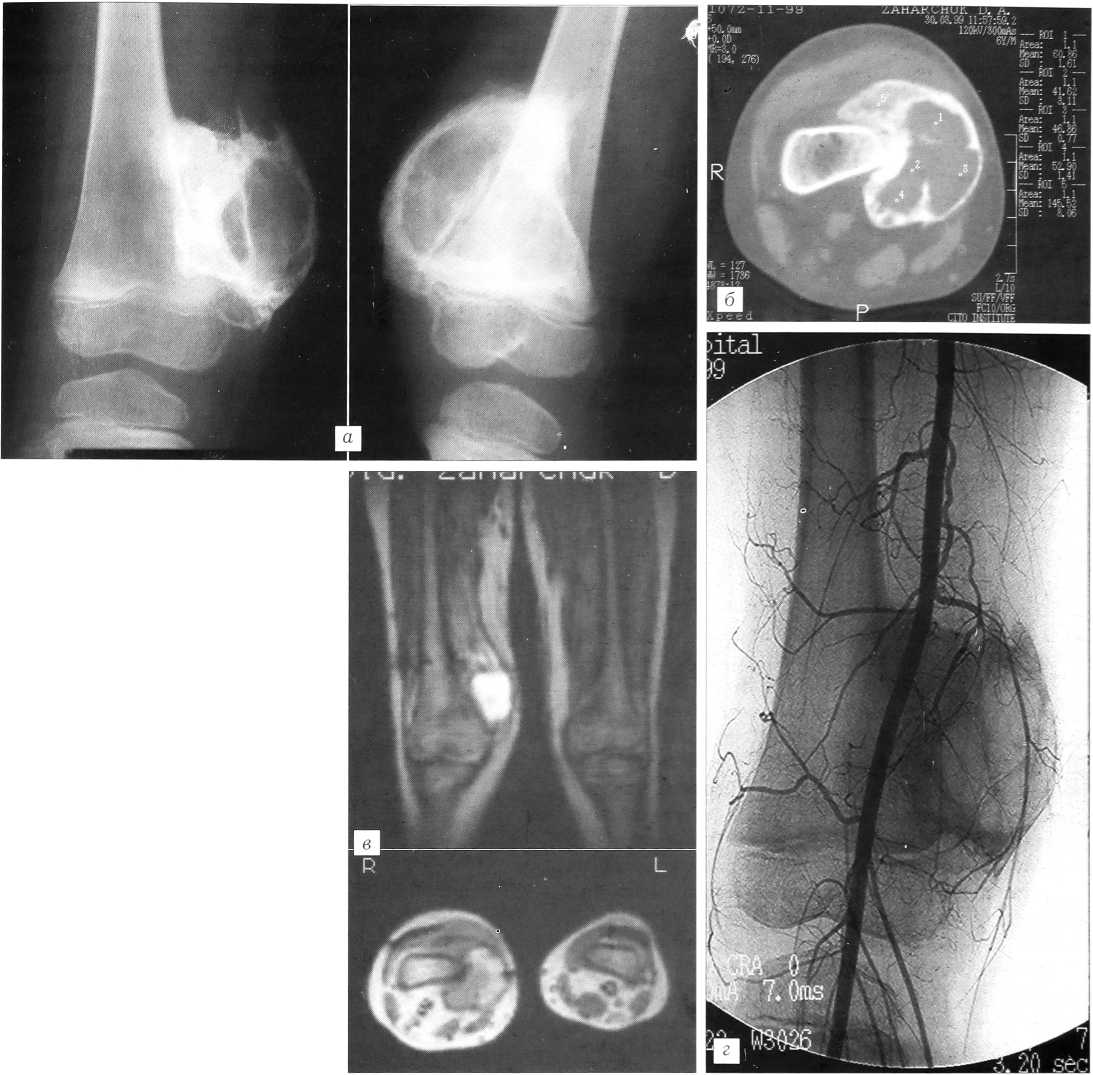

Рис. 4. Больной З. Гетеротопический оссификат правого коленного сустава. 2 мес от начала заболевания. а— рентгенограммы правого коленного сустава: неравномерная структура оссификата с участками разрежения и склероза. Четкий, неровный контур; б — компьютерные томограммы: неравномерное разрежение костной структуры в центре оссификата. Нечеткость границ между оссификатом и бедренной костью на ограниченном протяжении. Увеличение объема и нечеткость контуров m. vastus medialis; в — магнитно-резонансная томограмма: в режиме Т2 взвешенности изоинтенсивный гетерогенный сигнал от оссификата и гиперинтенсивный сигнал от m. vastus medialis.

Больной З., 6 лет, заболел через 3 дня после падения на правую ногу, согнутую в коленном суставе: по внутренней поверхности сустава появилась нарастающая припухлость. На сустав накладывался компресс с мазью Вишневского, иммобилизация не проводилась. Однократная пункция сустава и сеанс УВЧ-терапии усилили боль в суставе. Из разреза по медиальной поверхности сустава удалена гематома, взята ткань (биоптат) для исследования, по результатам которого злокачественного новообразования не выявлено. Кожа в области сустава покраснела, температура тела повысилась до 37,4°С. По поводу «гонита» проводились антибиотикотерапия, приточно-отточное промывание. Сустав увеличился в объеме, и спустя 2 мес от начала заболевания пациент был переведен в ЦИТО с диагнозом «рецидивирующий остеомиелит бедренной кости».

При поступлении: правый коленный сустав резко увеличен за счет неподвижной плотной припухлости по его переднемедиальной поверхности. Кожные покровы в области сустава горячие на ощупь. Визуально определяемых изменений кожи за исключением послеоперационных рубцов в месте проведения дренажной трубки нет. Окружность правого коленного сустава 33 см, левого — 23 см, окружность правого бедра 30 см, левого — 28 см. Объем движений в правом коленном суставе 180-160°, боли при движениях нет. Соматически здоров. Клинические и биохимические анализы крови и мочи в норме.

Спустя 2 мес от начала болезни в ЦИТО установлен диагноз: псевдозлокачественный гетеротопический оссификат.

На рентгенограммах правого коленного сустава по внутренней поверхности определяется дополнительное пароссальное образование костной плотности размером 7x6x6 см с неровным четким контуром. Структура очага неоднородная, с участками остеосклероза и мелкими кистами в центральных отделах. В проекции m. vastus medialis дифференцируются единичные оссификаты. Пароссальный оссификат вплотную прилежит к внутренней поверхности дистального метафиза бедренной кости (рис. 4, а).

При компьютерной томографии выявлено, что оссификат на ограниченном протяжении интимно связан с корковым слоем бедренной кости. В центре оссификата зона разрежения костной структуры с фестончатыми контурами. М. vastus medialis выше оссификата увеличена в объеме и не имеет четких контуров (рис. 4, б). На магнитно-резонансных томограммах в режиме Т2 взвешенности определяется гетерогенный изоинтенсивный сигнал от m. vastus midialis (рис. 4, в).

Рис. 5. Тот же больной З. через 4 мес от начала заболевания. а — рентгенограммы: большую часть оссификата занимает киста; б — компьютерная томограмма: киста имеет фестончатый контур и относительную плотность от 40 до 60 HU; в — магнитно-резонансные томограммы: в режиме Т1 взвешенности изоинтенсивный гетерогенный сигнал от оссификата. В режиме Т2 взвешенности гиперинтенсивный сигнал от оссификата и изоинтенсивный от m. vastus medialis; г — ангиограмма: смещение артериальных сосудов третьего порядка оссификатом.

Комплексное обследование позволило заключить, что «созревание» оссификата не закончено. Наложена гипсовая повязка и ребенок переведен под амбулаторное наблюдение. По снятии гипсовой повязки кожа спокойная, признаков воспаления нет. Движения в суставе не восстановились, в сохранившемся объеме (амплитуда 20°) безболезненны.

Через 4 мес на рентгенограммах размеры оссификата прежние. Центральные отделы его заняты кистой, которая значительно увеличилась (рис. 5, а).

Компьютерная томография: кистозная полость занимает большую часть оссификата, имеет фестончатые контуры. Относительная плотность содержимого кисты 40-60 HU (рис. 5, б).

Магнитно-резонансная томография: в режиме Т1 взвешенности сигнал от оссификата гетерогенный изоинтенсивный, в Т2 — гиперинтенсивный. Сигнал от m. vastus medialis в режиме Т2 взвешенности стал изоинтенсивным (рис. 5, в).

На ангиограммах правого коленного сустава нарушений кровообращения не выявлено за исключением смещения оссификатом артериальных сосудов третьего порядка по внутренней поверхности бедренной кости (рис. 5, г).

По результатам проведенных в динамике исследований подтверждено заключение о наличии у больного гетеротопического оссификата. Имеющиеся структурные изменения расценены как проявления его «созревания» и обратного развития.

Спустя 6 мес от начала заболевания, после 4-месячной иммобилизации гипсовой повязкой ребенок подвергнут хирургическому лечению. Медиальным разрезом в нижней трети бедра обнажено костной плотности образование размером 7x6x6 см, покрытое соединительнотканной капсулой. На двух участках оно срослось с бедренной костью, из-за чего неподвижно. При пункции оссификата внутрикостной иглой получено около 20 мл соломенно-желтого цвета жидкости (как после отстоявшейся гематомы), отличающейся от синовиальной жидкости меньшей вязкостью. Медиальная поверхность и проксимальные отделы оссификата интимно и прочно спаяны с m. vastus intermedius и т. vastus medialis, часть верхнего заворота сустава входит в псевдокапсулу оссификата. Эти изменения и послужили причиной «блокады» сустава. После пересечения костных мостиков и мягкотканных спаек оссификат удален. Объем движений удалось восстановить на операционном столе. Костные раны заделаны воском, произведен тщательный гемостаз, установлен активный дренаж. Прилежащие мягкие ткани инфильтрированы раствором гидрокортизона в дозе 50 мг. Эта процедура дважды повторена при перевязках. Иммобилизация гипсовой повязкой продолжалась 21 день. По снятии гипсовой повязки — восстановительное лечение.